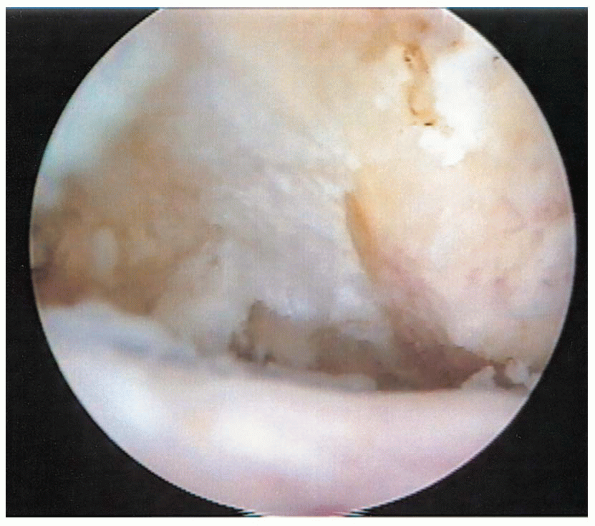

rotator cuff tear is inspected. Tear size, morphology, and mobility is

assessed through both the posterior and anterior portals. A traction

suture or arthroscopic grasper can be used to assess the mobility of

the tear (Fig. 2-18). If desired, a soft tissue elevator can be used to release articular and bursalsided adhesions.

![]() |

|

FIGURE 2-18. Arthroscopic assessment of tear mobility using a traction suture.